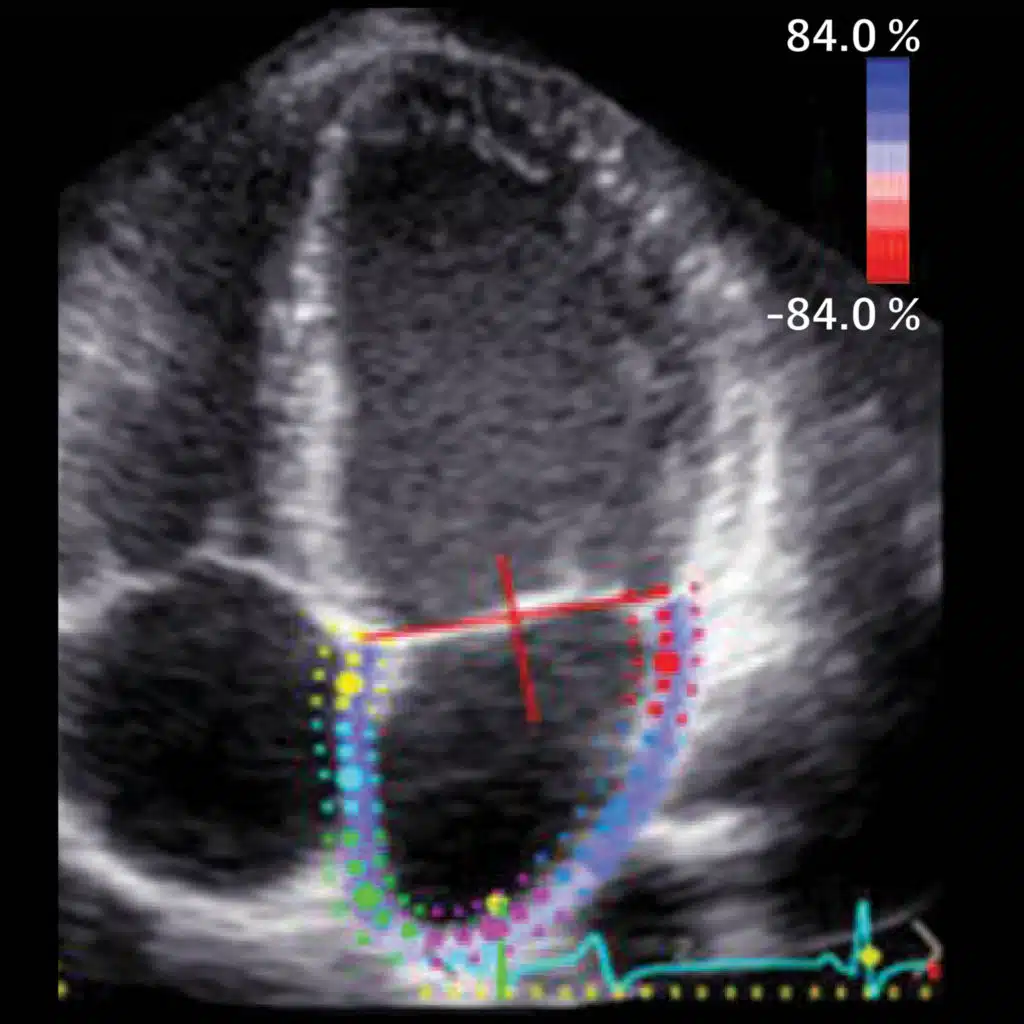

AI and Clinical Practice—How AI Could Advance Human Heart Discoveries and Improve Care

Can AI enhance the speed and efficiency of interpreting ultrasounds and echocardiograms, thereby minimizing diagnostic errors? In this Q&A, Rima Arnaout, MD, a cardiologist and associate professor of medicine at the University of California-San Francisco, joins JAMA's Editor i ...